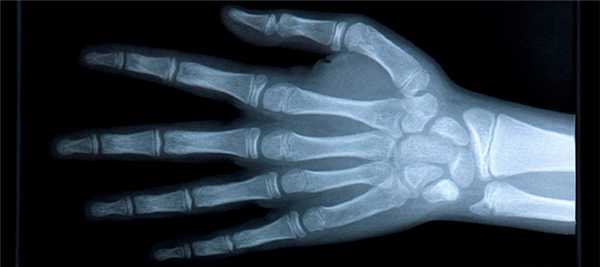

- Прямая проекция. Для такой съёмки кисть укладывается горизонтально, на стол - тыльной стороной или ладонью. Лучи рентгена будут проходить через кисть перпендикулярно кассете с плёнкой. На таком снимке будут определяться все кости запястья, за исключением гороховидной. Также будут видны лучезапястный сустав, пястные кости, запястно-пястные суставы, межзапястный сустав и фаланги пальцев.

- Боковая проекция. Для такой съёмки нужно расположить ладонь ульнарным краем на кассете. Большой палец при этом нужно слегка отвести вперёд. На таком снимке будут хорошо видны контуры костей запястья, пястные кости, фаланги. Такая проекция оказывается наиболее полезной в травматологии, когда нужно выявить смещения пястных костей.

- Косая тыльная проекция. Кисть нужно расположить так, чтобы её тыльная поверхность образовывала угол 45° с кассетой. Такой снимок покажет состояние трёхгранной кости, гороховидной, крючковатой, а также первой и пятой пястных костей.

- Косая ладонная проекция. Кисть располагается так, чтобы ладонная поверхность образовывала угол 45° с кассетой. На этом снимке будет видно ладьевидную, трапециевидную кости и кость-трапецию.

Расшифровка результатов

Расшифровку рентгена кистей рук делает специалист-рентгенолог сразу после завершения съёмки. Он оценивает взаимное расположение костей кисти, их соединение между собой, целостность. Также уделяется внимание оценке структуры и плотности костей.

Нормальные показатели

В норме кости кистей рук должны иметь однородную структуру. На снимках не должно быть затемнений на белых участках. Между костями должна присутствовать щель.